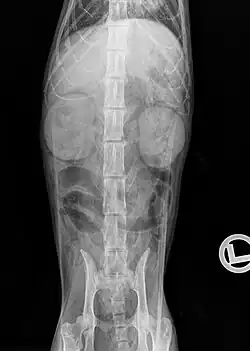

Mit einer Röntgenuntersuchung lassen sich Größen-, Dichte- und Lageveränderungen der Nieren sowie einige Harnsteine (Struvit- und Calciumoxalatsteine sind „röntgendicht“) und Weichteilverkalkungen nachweisen. Bei stark abgemagerten Katzen oder Flüssigkeitsansammlungen im Retroperitonealraum ist die Niere im Röntgenbild jedoch aufgrund der daraus resultierenden Kontrastminderung nur bedingt darstellbar. Eine höhere diagnostische Aussage hat die Ausscheidungsurographie, bei der ein röntgendichtes Kontrastmittel (z. B. Iopamidol, Iohexol) in die Blutbahn gespritzt und dessen Ausscheidung über die Nieren röntgenologisch erfasst wird. Damit lassen sich Durchblutungsstörungen, Funktionsstörungen der Nierenkörperchen und Verlegungen der Abflusswege nachweisen.[22]